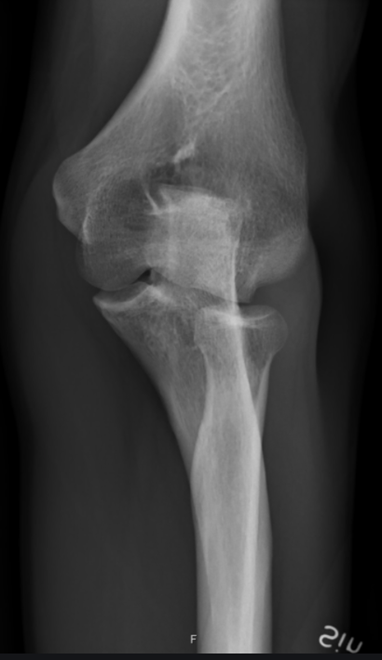

these 2 images of the elbow are in what position (2 for 1!) CR perpendicular to humerus and then CR perpendicular to forearm

this acute flexion of the elbow image is showing the __ __

AP Partial Flexion, Acute Flexion

what 2 position (2 images each) compromises for an AP elbow radiograph